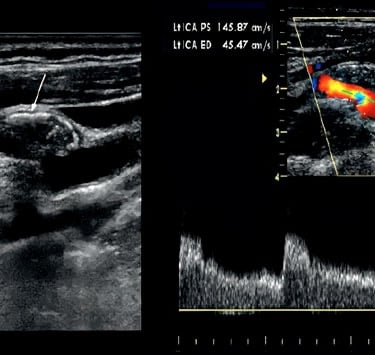

Our Vascular course unfolds as a protocol-driven journey through arterial, venous, and physiologic Doppler mastery.

We begin by aligning participants around the core vascular anatomy and hemodynamic principles that make each Doppler signal meaningful. Early scanning sessions focus on smooth image acquisition and accurate angle alignment across major vascular beds.

As your foundation solidifies, scanning expands to encompass a systematic, total-body protocol — carotid, upper and lower extremities, abdominal vessels, transcranial windows, and venous insufficiency surveys — all with immediate faculty feedback. Doppler interpretation is integrated alongside anatomy, teaching you how to recognize and quantify pathology rather than memorizing isolated signs.